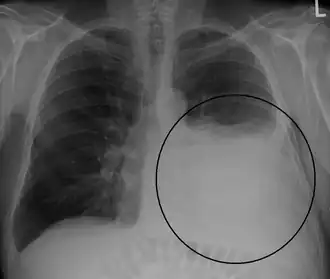

Radiografía de tórax que muestra un derrame pleural en el pulmón izquierdo (señalado con un círculo) | ||

El derrame se hace visible en la radiografía cuando es mayor de 75 ml, puede aparecer libre o loculado. En caso de que existan dudas, es recomendable la realización de una radiografía en decúbito lateral del lado afecto. El derrame pleural puede presentar imágenes radiológicas atípicas como:

- La imagen de la radiografía de tórax en el derrame pleural es usualmente característica a 200 ml de líquido pleural (LP) producen borramiento de los ángulos cardiofrénico y costodiafragmático. 50 a 75 ml de LP producen borramiento del ángulo costodiafragmático posterior en la radiografía lateral, observándose el denominado “signo del menisco”. La sensibilidad de la radiografía de tórax para detectar DP es 24-100% con especificidad 85-100% y la sensibilidad para detección del DP por utrasonido es 93% con especificidad 96%.